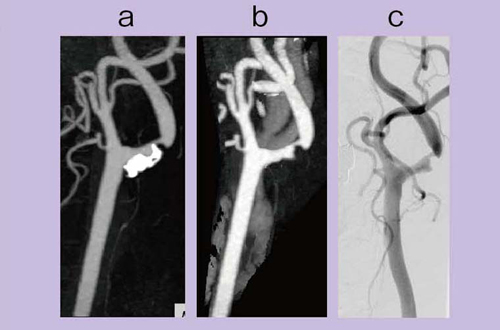

図7 aのコンベンショナルCTAのMIP画像では,かなり強い石灰化が認められるが,bのDEイメージング骨除去画像では石灰化がきれいに抜けていて,cのDSAとほぼ同様な画像が得られ,狭窄率を正確に計測可能である。

石灰化のある13症例(18断面)の狭窄率について,骨除去CTAとDSAを比較した結果,非常に良い相関を示す結果が出ている。

図7 頸部血管狭窄

a:コンベンショナルCTA

b:DE骨除去CTA

c:DSA